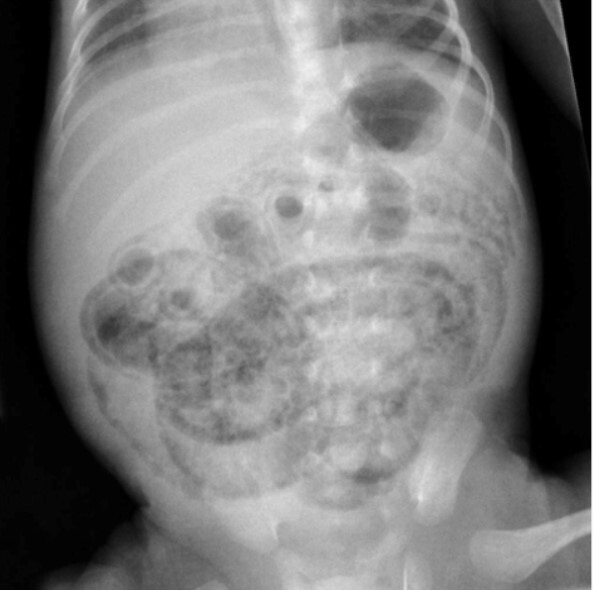

Segun los criterios de Bell . ¿ Que estadio comprende esta radiografia ?

llA = Caso confirmado , presencia de neumatosis en Radiografía Abdominal